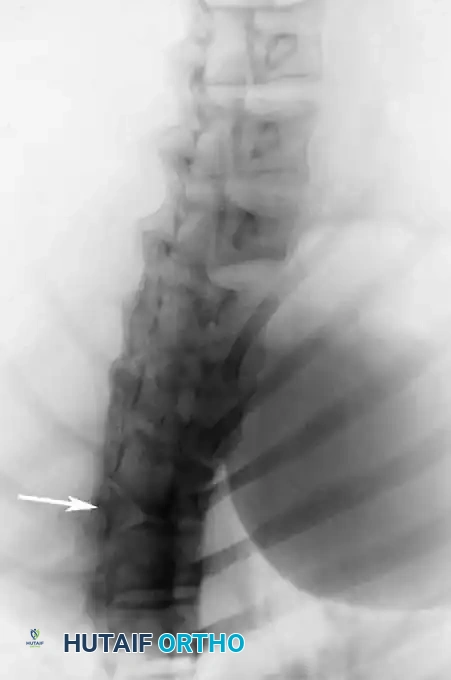

1. Plain Radiographs:

Detailed anteroposterior (AP) and lateral radiographs are essential. Flexion and extension lateral views help determine the rigidity of the kyphosis and identify any compensatory hypermobility or instability in adjacent segments.

2. Computed Tomography (CT) with 3D Reconstruction:

CT is invaluable for defining the complex bony architecture. It delineates the exact extent of formation/segmentation failure and helps predict the trajectory of the deformity (kyphosis vs. kyphoscoliosis). However, CT cannot assess the growth potential of the cartilaginous anlage.